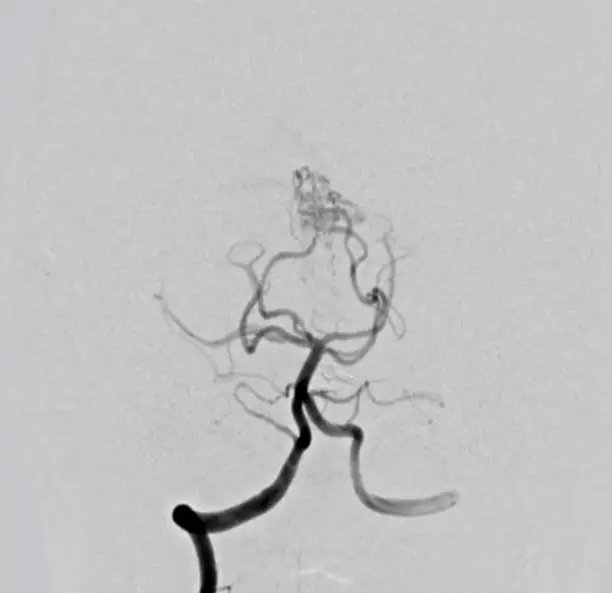

뇌혈관 조영술은 뇌혈관 상태를 정확히 진단하기 위해 시행되는 중요한 검사 중 하나입니다. 이 검사는 혈관의 구조를 확인하고 이상을 발견하는 데 매우 유용하며, 특히 뇌졸중, 뇌동맥류, 혈관 협착 등 중대한 질환을 진단하는 데 필수적입니다. 검사 자체는 다소 침습적이고 방사선과 조영제를 사용하므로 이에 따른 부작용 가능성도 존재하지만, 그 중요성 때문에 많은 환자들이 이 검사를 필요로 합니다. 이제 뇌혈관 조영술의 비용, 검사 절차, 부작용 및 보험 처리 등에 대해 자세히 알아보겠습니다.

뇌혈관 조영술은 고도로 전문적인 장비를 사용하여 혈관의 상태를 확인하는 검사입니다. 이 과정에서 카테터를 혈관에 삽입하고, 조영제를 주입한 후 X-ray를 통해 혈관을 촬영합니다. 일반적으로 팔이나 사타구니 부위에 카테터를 삽입하며, 혈관을 통해 뇌로 조영제를 전달합니다. 조영제가 혈관을 통과하면, 의료진은 혈관의 상태를 실시간으로 확인할 수 있습니다.